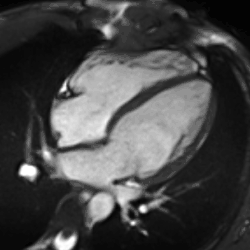

Partial Anomalous Pulmonary Venous Drainage by CMR

Heart function using cine imaging

Functional and structural information is acquired using bSSFP cine sequences. These are usually retrospectively-gated and have intrinsically high contrast in cardiac imaging due to the relatively high T2:T1 ratio of blood compared to myocardium. Images are typically planned sequentially to achieve the standard cardiac planes used for assessment. Turbulent flow causes dephasing and signal loss allowing valvular disease to be qualitatively appreciated. The left ventricular short axis cines are acquired from base to apex and are used for quantifying end-diastolic and end-systolic volumes, as well as myocardial mass. Tagging sequences excite a grid pattern that deforms with cardiac contraction allowing strain to be assessed.